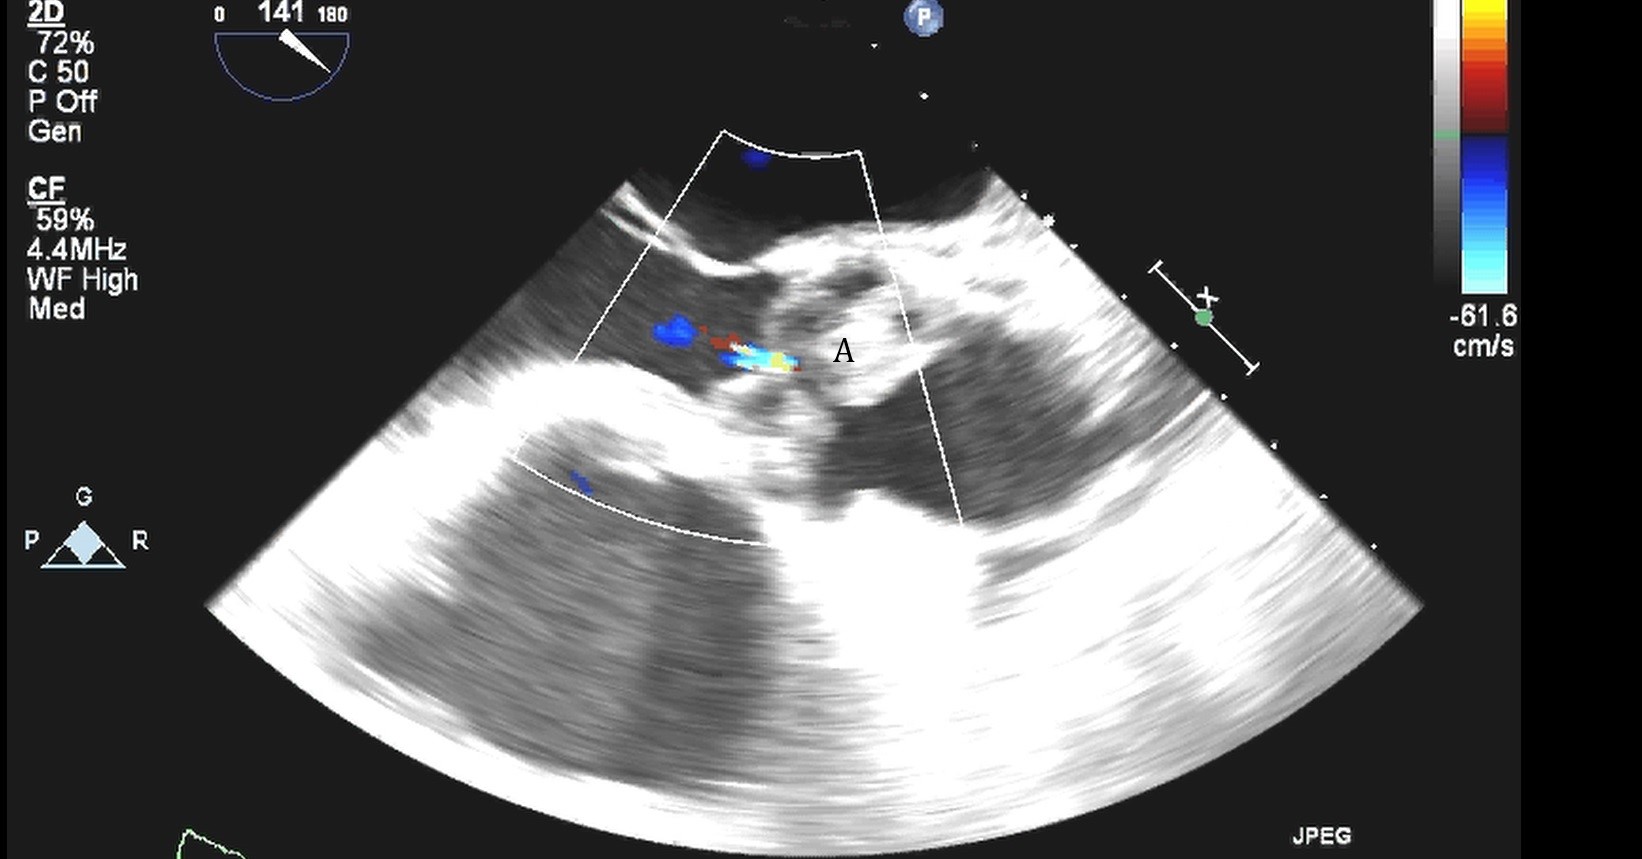

The intra-aortic balloon pump is a percutaneously placed counter pulsation device which helps in decreasing afterload as well as augmenting coronary perfusion. Initially developed in the 1960s it is the oldest MCS device and given its simplicity, cost effectiveness, and ease to implant and explant, it is the most commonly used temporary support device [6]. Although it is typically placed in the cardiac catheterization lab under fluoroscopic guidance, TEE can be utilized to help in its placement in the intubated patient in the intra-operative setting. The femoral artery is the most common site of placement however they can on occasion be placed in alternative sites such as the axillary artery or directly into the aorta [7, 8]. When placed via the femoral artery, it is threaded over a guidewire. TEE can be used to visualize both the guidewire as well as the tip of the IABP catheter during placement (Fig. 1) [9]. Ideal positioning of the balloon tip is 1–2 cm distal to the left subclavian artery to derive maximal hemodynamic benefit [10]. Positioning can be confirmed by visualizing the descending aorta and then withdrawing the TEE probe until the left subclavian artery and aortic arch are visualized. Upon activation of the balloon pump the gas filled balloon will cause shadowing and reverberation artifacts (Fig. 2). Its presence can be used as confirmation of proper function of the device. If these artifacts are not seen or bubbles are visualized in the aorta, rupture of the IABP should be suspected [9]. In addition to hemodynamic monitoring with a Swan-Ganz catheter, TTE can be used to monitor LV function after IABP placement and can help guide weaning of IABP support. It can also visualize any new or worsening aortic regurgitation. Given that IABPs work by reducing afterload, on rare occasions they can precipitate dynamic outflow tract obstruction and paradoxically worsen cardiogenic shock. Examples include patients with a relatively preserved basal or septal myocardial function in scenarios such as takotsubo cardiomyopathy or acute myocardial infarctions. Doppler imaging and color flow doppler can be used to identify such scenarios [11].

Fig. 1.TEE demonstrating IABP in descending aorta (A).

TEE demonstrating IABP in descending aorta (A) with reverberation artifact seen behind it upon activation (B).